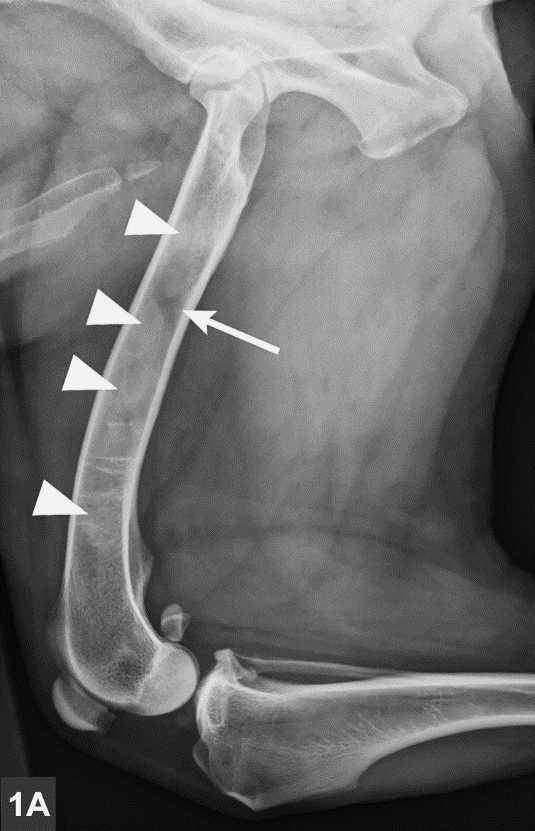

Určenie ochorenia prebieha na základe príznakov. Diagnózu potvrdzuje röntgen. V začiatku ochorenia sa vyskytuje nepatrné zvýšenie kostnej hustoty v strednej časti postihnutej kosti. V strednej fáze sa vnútro kosti stáva škvrnité, povrch kosti je drsný. V poslednej fáze je síce kosť stále škvrnitá, no pomaly sa vracia späť k normálu. .